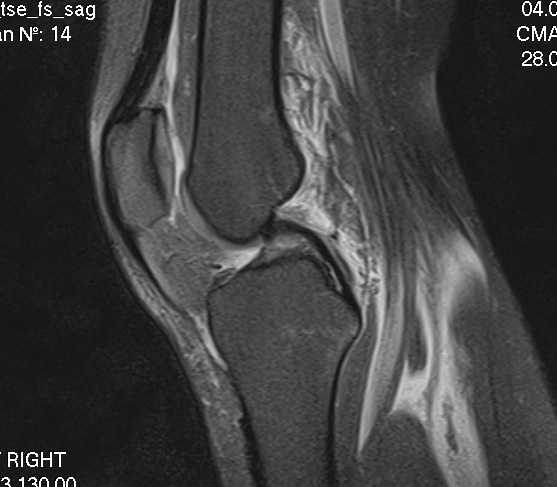

"Итак, после МРТ стало понятно, что у меня полностью оторвана передняя крестообразная связка. То есть, нога "гуляет" в колене. Это можно увидеть на фотографии МРТ, которую я прилагаю. На ней отчетливо видно заднюю крестообразную связку (она темная, сочетает бедренную и берцовую кость), а вот от передней видно только куски", - рассказала женщина.